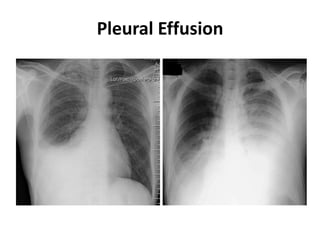

Pleural Effusion

How to detect minimal

pleural effusion ???

• CXR-PA: 150-175 ml

• CXR-lateral decubitus:

10-50 ml

• USG thorax: 3-5 ml